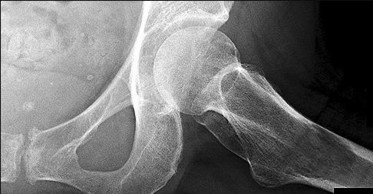

A 28-year-old male sustains a high-energy Pauwels type III femoral neck fracture.

Compared to a Pauwels type I fracture, which of the following biomechanical forces is most significantly increased at the fracture site?

Explanation

The Pauwels classification of femoral neck fractures is based on the angle of the fracture line relative to the horizontal plane. A type III fracture has an angle greater than 50 degrees, making it more vertically oriented. This vertical orientation significantly increases shear forces across the fracture site, leading to a higher risk of varus collapse, nonunion, and fixation failure.